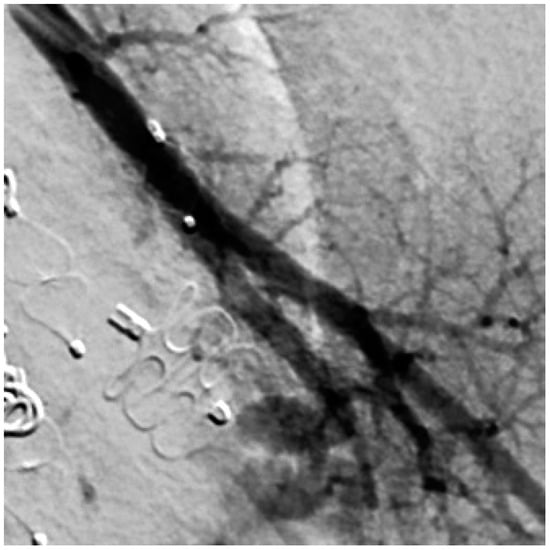

When assessing the implanted embolization material, it was also noticed that some of the coils in the DSA appeared thinner than others. Figure 11 shows a Nester® Embolization Coil from Cook Medical, which is available in a thickness of 0.035 inch and is regularly used in our department. In ten patients with a total of 29 recanalized AV shunts, the implanted coils appeared thinner than those used at our department, with these accounting for 45.3% of the total number of recanalized AV shunts. An example is therefore shown in Figure 12. In this context, a possible correlation between the use of coils with a lower thickness and a possible increased recanalization rate after embolization was discussed.

Figure 11. Nester® Embolization Coils with a thickness of 0.035 inch.

Figure 12. Coils of a patient with external treatment and which appear thinner than the Nester® Embolization Coil.